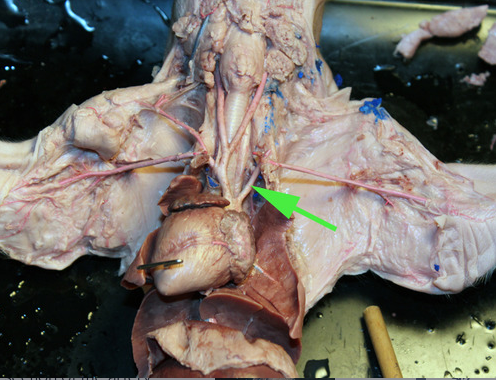

The vessel marked by the green arrow is a coronary artery

The vessel marked by the green arrow is a branch of a pulmonary artery

The vessel marked by the green arrow is a branch of a

pulmonary artery.